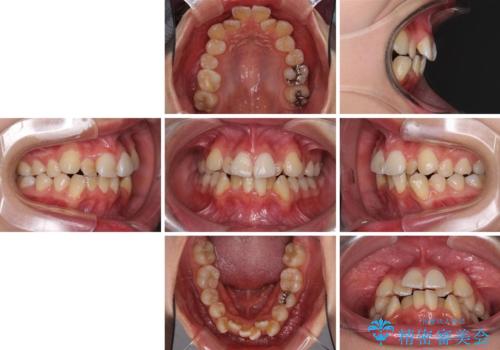

- 上下前歯のデコボコと、それによる磨きづらさを気にして来院された患者様です。

叢生解消のため、上下左右第一小臼歯4本を抜歯し、ワイヤー装置にて矯正治療を行うこととしました。

半年ほどで前歯のデコボコは改善され、汚れの溜まりやすさは解消されました。

抜歯スペースを閉じるために期間がかかりましたが、当初予定通り2年強で終えることができました。